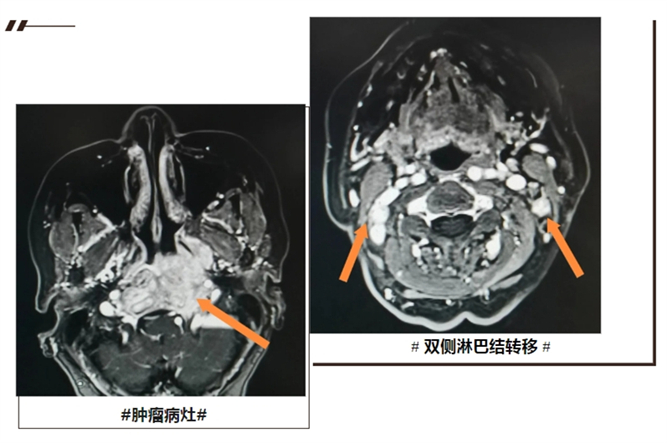

半年前,來(lái)自城區(qū)的王阿姨(化名)斷斷續(xù)續(xù)出現(xiàn)頭痛,一開(kāi)始并未在意,期間還有頭暈、復(fù)視的情況,直到出現(xiàn)“涕中帶血”癥狀,才前往醫(yī)院就診。核磁檢查顯示,鼻咽部占位性病變伴雙側(cè)頸部多發(fā)腫大淋巴結(jié),考慮: 鼻咽癌!

王阿姨入院后,進(jìn)行了電子纖維鼻咽鏡、全身PET-CT等相關(guān)檢查。明確病理:中分化鱗狀細(xì)胞癌,分期:T4N3M0 VI期。

北京腫瘤專(zhuān)家會(huì)診后決定給予鼻咽癌根治性放射治療,治療前后對(duì)比可見(jiàn),病灶完全消失。